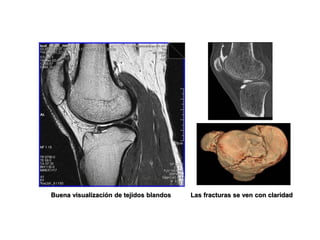

Buena visualización de tejidos blandos Las fracturas se ven con claridad

Buena visualización detejidos blandos Las fracturas se ven con claridad